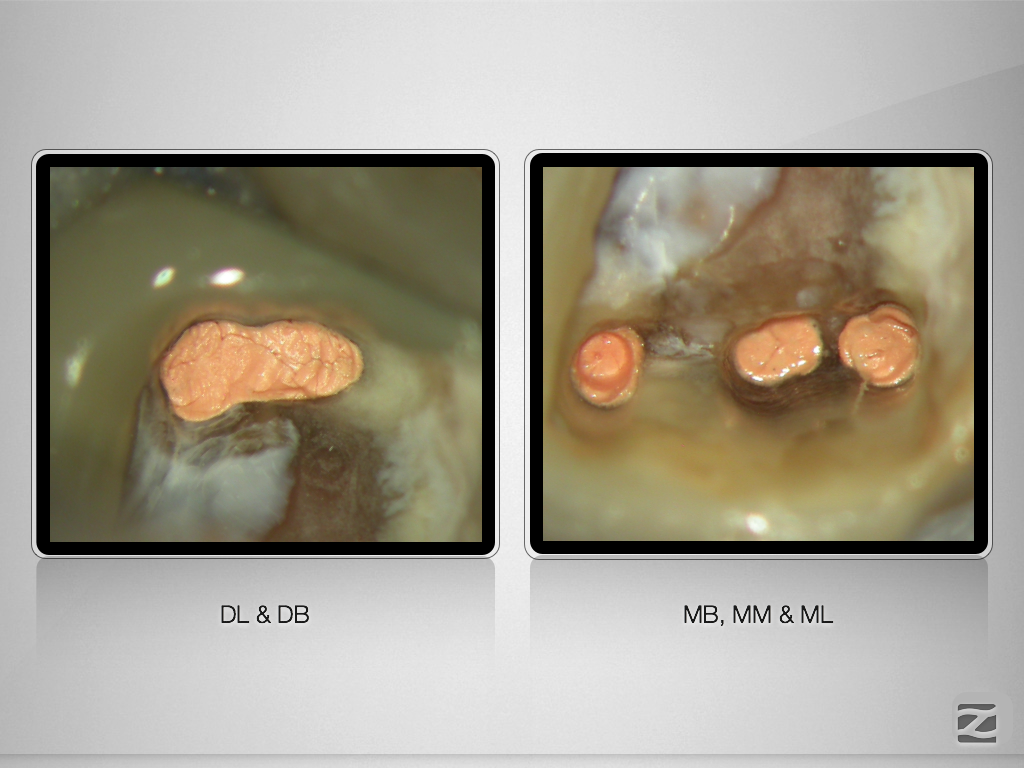

36D.007

Anatomie unterer Molaren (10)